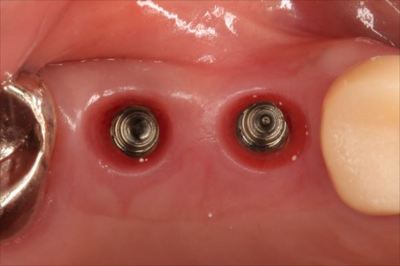

アバットメントのスキャニングのため、ヒーリングキャップを取り外しました。

アップです。

白い粒子はハミガキ剤に含まれる研磨粒子と考えられます。

天然歯においては歯肉溝がインプラントより浅いため、問題ないものと思われますが

インプラントの場合は歯肉溝に相当する部分が深いため、研磨粒子の残存・歯肉への迷入が起こりやすいようです。

研磨粒子が残っていても、すぐさまそれが問題となるとは限りませんが、本来存在して欲しくないものですので注意が必要と考えます。